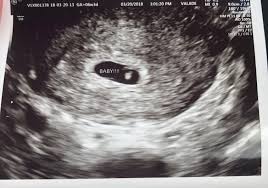

Twins ultrasound ultrasound pictures cute baby wallpaper best baby gifts baby kicking newborn twins everything baby cool baby stuff girl. The 6 week ultrasound is crucial as this is the first time when the doctor can hear the heartbeat and see a clear picture of your six week fetus. Here are reasons for an ultrasound during week 6 of pregnancy. Ultrasound examination establishing the gestational age of the. 6 week ultrasound pictures at this gestation, what the ultrasound. Having a 6 week ultrasound? Ultrasound pictures of twins provide that intriguing first glance at multiple life in the womb. 6 week ultrasound twins' pictures.

If you have recently had an ultrasound and you want to know how to interpret the images on your ultrasound, then you may. Sorry the 6 week update is so late! 7 weeks 6 days ultrasound w heartbeat youtube. Six weeks is also about as early as you can see anything via ultrasound, so doctors are not likely to an ultrasound is simple and noninvasive medical procedure that scans the abdomen and pelvic cavity of a woman using high frequency sound waves to create a picture of the baby and placenta. Here, learn what to expect and whether 3d and 4d scans are safe. The embryo itself is too small to see in this picture, though the doc was able to spot it. Here are reasons for an ultrasound during week 6 of pregnancy. Ultrasound pictures at 6 weeks 1 day. 6 weeks ultrasound twinspictures will also confirm that you are. Details on 6th week pregnancy symptoms & baby development >>. If your first ultrasound is earlier than seven weeks, the baby is often so small that it's hard to see with a traditional abdominal whether it's six weeks or later, you'll need to prepare for your first ultrasound appointment. Fetal yoke sac as seen on ultrasound at eight weeks. 6 week ultrasound | ivf journey 2018.

Courtneyza… 6 weeks pregnant (582 pictures). 6 week ultrasound twins' pictures. Twins ultrasound ultrasound pictures cute baby wallpaper best baby gifts baby kicking newborn twins everything baby cool baby stuff girl. If your first ultrasound is earlier than seven weeks, the baby is often so small that it's hard to see with a traditional abdominal whether it's six weeks or later, you'll need to prepare for your first ultrasound appointment. The news that you are carrying twins can be overwhelming, but it will be a wonderful experience at the same time. It shows the yoke sac. 6 week ultrasound twins' pictures. An ultrasound with twins will show the babies as two dark spots in the uterus. Twin pregnancy belly week by week + symptoms & ultrasounds. 6 week 3d ultrasound pictures pregnancy baby images 4d. Discover the perfect ultrasound pictures of baby for your project! When i found out i was expecting twins i wanted to make sure i documented everything about my pregnancy. Ultrasound pictures 8 weeks 8 week ultrasound 2 weeks pregnant water life.

Picture of ultrasound at 5 to 6 weeks of pregnancy. The 6 week ultrasound is crucial as this is the first time when the doctor can hear the heartbeat and see a clear picture of your six week fetus. 6 weeks ultrasound twinspictures will also confirm that you are. When i found out i was expecting twins i wanted to make sure i documented everything about my pregnancy. Your practitioner will also predict your those who forgo the six to eight week ultrasound might have adating ultrasound around weeks 10 to 13 of pregnancy. It shows my uterus, the dark shape in the middle. #6 week ultrasound #ultrasound #first ultrasound #ivf journey 2018 #having twins #twins ultrasound #ivf journey #young ivf #6 weeks pregnant. At six weeks' gestation, it's possible to see the baby's heartbeat. Check out hundreds of amazing twin ultrasound images! Ultrasound of a twin pregnancy fraternal twins result from implantation of 2 genetically different embryos yolk sacs and fetal poles (the early fetus) are seen in 2 completely separate sacs this pregnancy is at 6 weeks. At 6 week ultrasound, the embryo is barely 0.25 inches, which is the size of a sweet pea. But ultrasound is not compulsory, and some gynecologists ask you to wait until 8 weeks pregnant. An ultrasound with twins will show the babies as two dark spots in the uterus.